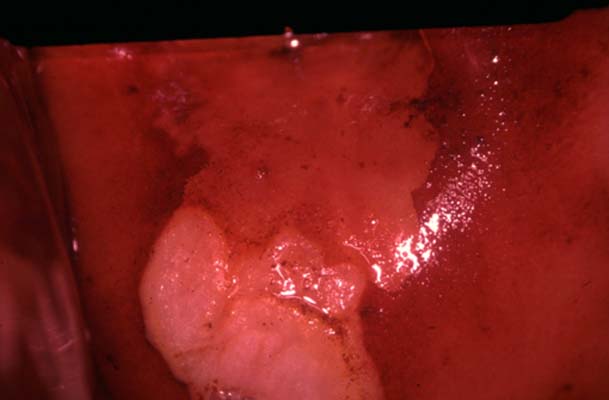

TAGI avec leucoplasie